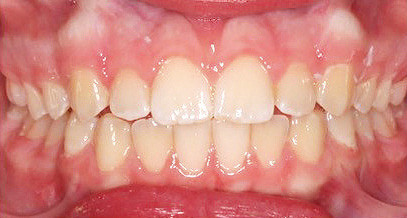

Klinisches Fallbeispiel 2 (Abb. 2a–y)

Distalbiss und tiefer Biss bei einem zwölfjährigen Mädchen. Die Behandlung erfolgte mit Invisalign und Precision Wings. Insgesamt waren zwei Schienensätze notwendig. Die Gesamtbehandlung dauerte 18 Monate.Bei der Planung des ClinCheck wurde der tiefe Biss vorwiegend über eine Intrusion der Unterkieferfront behoben, um die Lachlinie der Patientin nicht negativ zu beeinflussen. Die Oberkieferfront wurde nur retrudiert, jedoch vertikal nicht intrudiert. Während der Phase des Mandibular Advancement wurde die Wirkung der Precision Wings durch den Einsatz von Klasse II-Gummizügen unterstützt. Schlussendlich wurde auch der hängenden Okklusionsebene durch eine einseitige Intrusion der Molaren im ersten Quadranten Rechnung getragen.